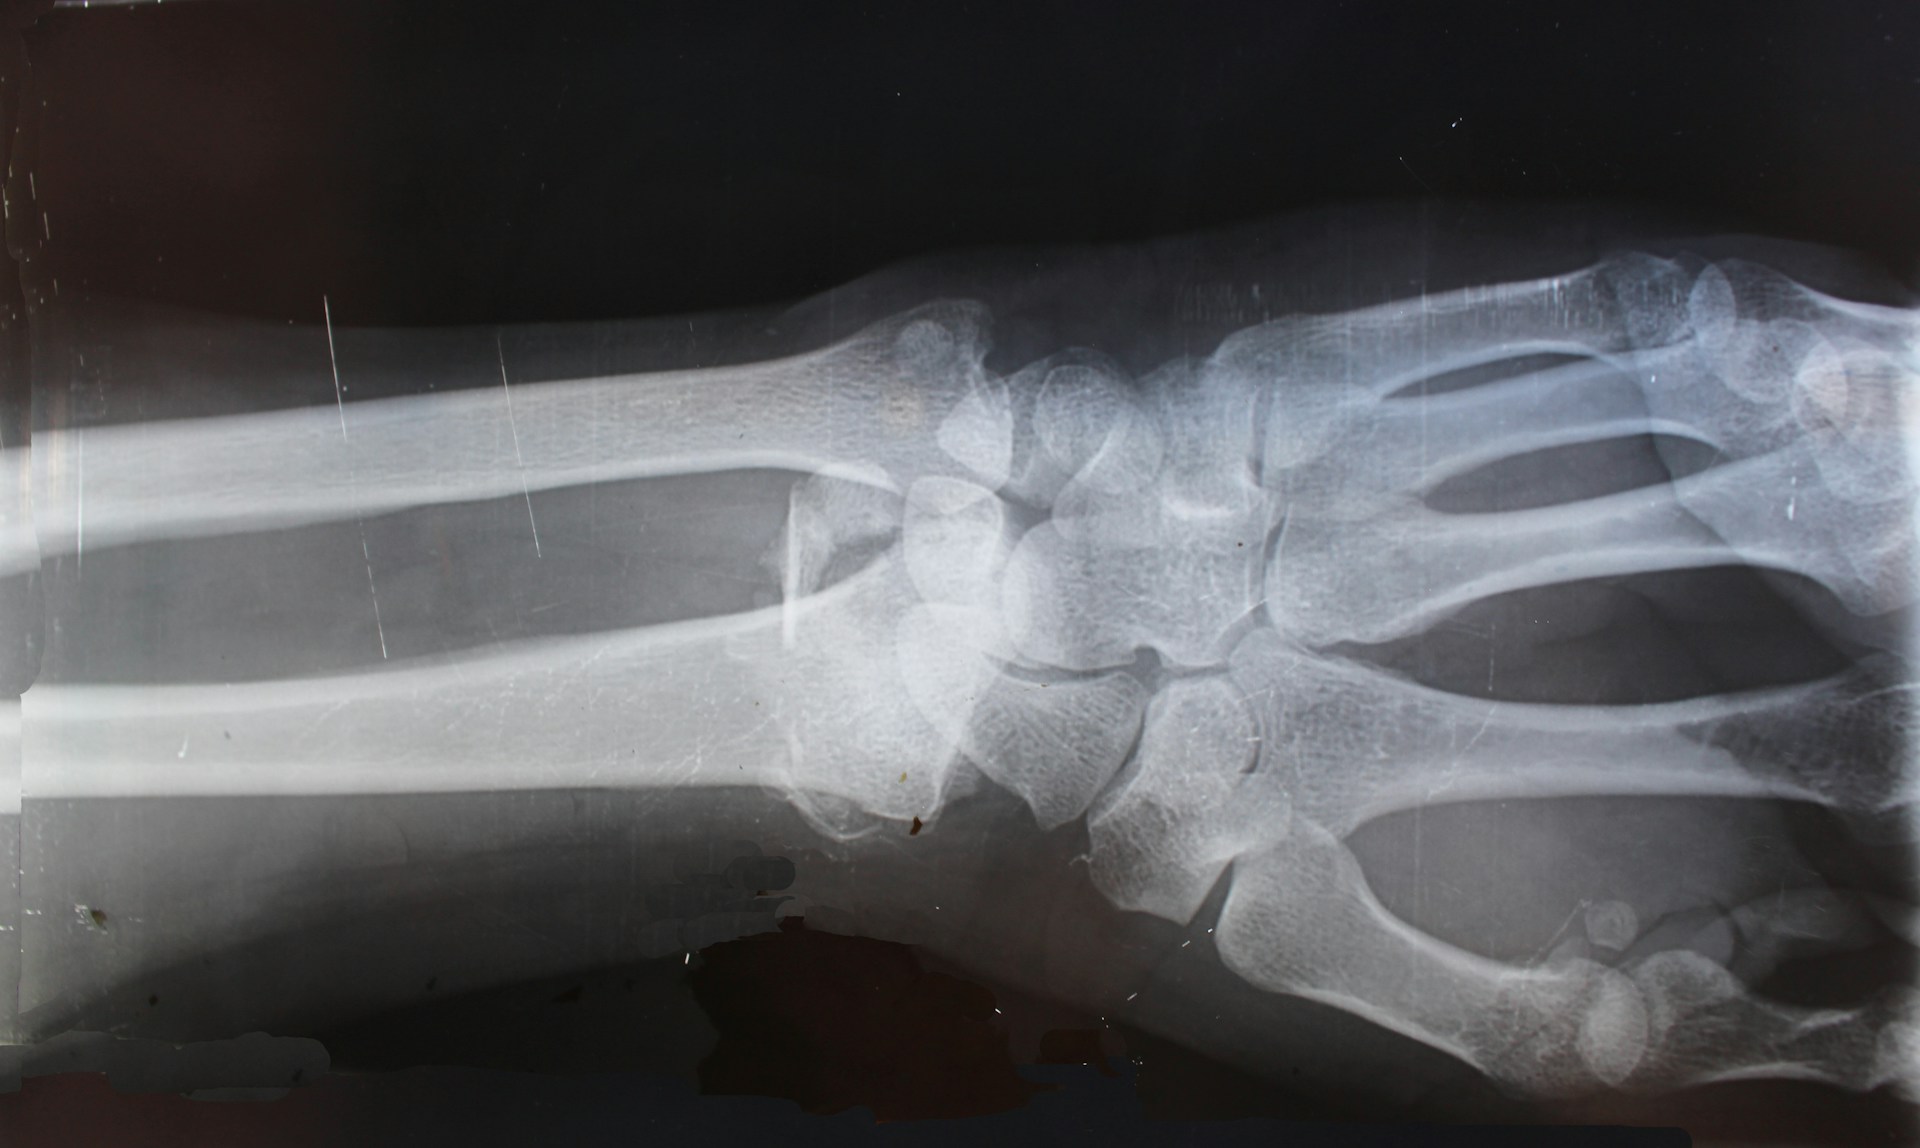

Rentgen dijagnostika

Rentgen ( X-zraci) dijagnostika je jedini način da se sigurno provere prelomi kostiju kod dece. Ako dete trpi veliki veliki bol, ima otečenu ruku ili nogu, otežano se kreće, potrebna je procena doktora. Prelomi su nezgodni jer se mogu javiti prelomi i osovine kosti, ali i zlgoba kao i deo kostiju.

Dečije kosti su nežne i osetljive jer su, naravno, mekše, imaju mekšu hrskavicu blizu kraja kosti, koje dopušta kostima da rastu i produžavaju se. Budući da hrskavica nema kalcijum, ona se na rentgenskom snimku pojavljuje kao tanka nit. Budući da je kost mekša u tom delu koji raste, uobičajeno je da se u ovom delu javljuju prelomi kosti kod dece. Ako su pravilno lečene, frakture na ruci i ručnom zglobu neće se kasnije deformisati.

Dijagnoza se postavlja na osnovu anamneze, pregleda, pregleda skenerom i drugim aparatima. Nakon određivanja stepena preloma, radi se Rtg nalaza i klinička slika i donosi se odluka o daljem lečenju deteta.